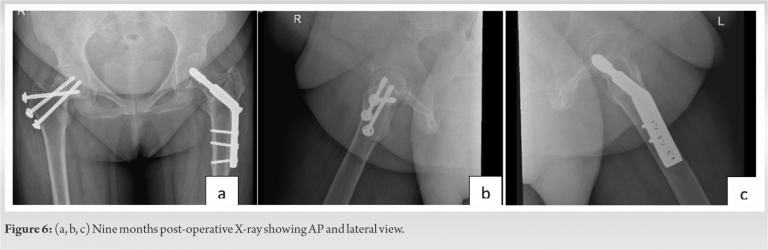

As lockdown was enforced from March 23, 2020, in COVID-19 pandemic, restricting mobility and because of fear of contracting COVID, she did not attend OPD. Telephonic conversation was done to know her condition and it was found satisfactory. Patient physically reported at the end of 3rd month. X-ray of pelvis with both hips was taken which showed well-advanced stage of union. We wanted her to start weight bearing on the left lower limb (and no weight bearing on right lower limb) but she was apprehensive to use crutches because of post-injury discomfort in right shoulder. She started this in 4th month as per telephonic conversation. After 6 months from the surgery, she was readmitted in our hospital under the nephrology unit with reduced hemoglobin. She was treated and two units of packed cell were transfused. Her X-ray showed fractures well united (Fig. 5) and she could walk without support. She was asked to follow-up at 3 months interval. At last follow-up of 9 months her X-ray showed well united fracture in both AP and lateral view (Fig. 6a, b, c) and she had good range of movement in both hips.